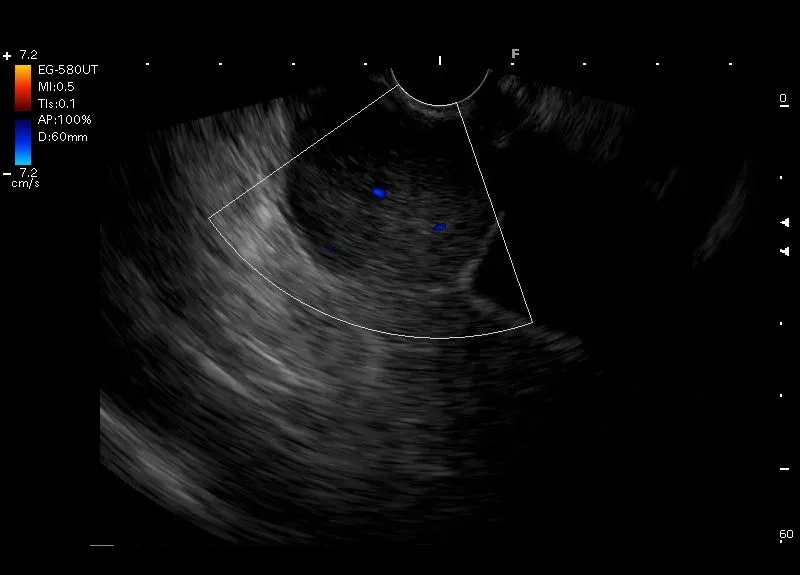

Wywodząca się z muscularis propriae ściany żołądka, owalna zmiana, z drobnymi bezechowymi przestrzeniami oraz widocznymi w badaniu doppler miejscami przepływu naczyniowego - w pierwszej kolejności obraz odpowiada GIST.